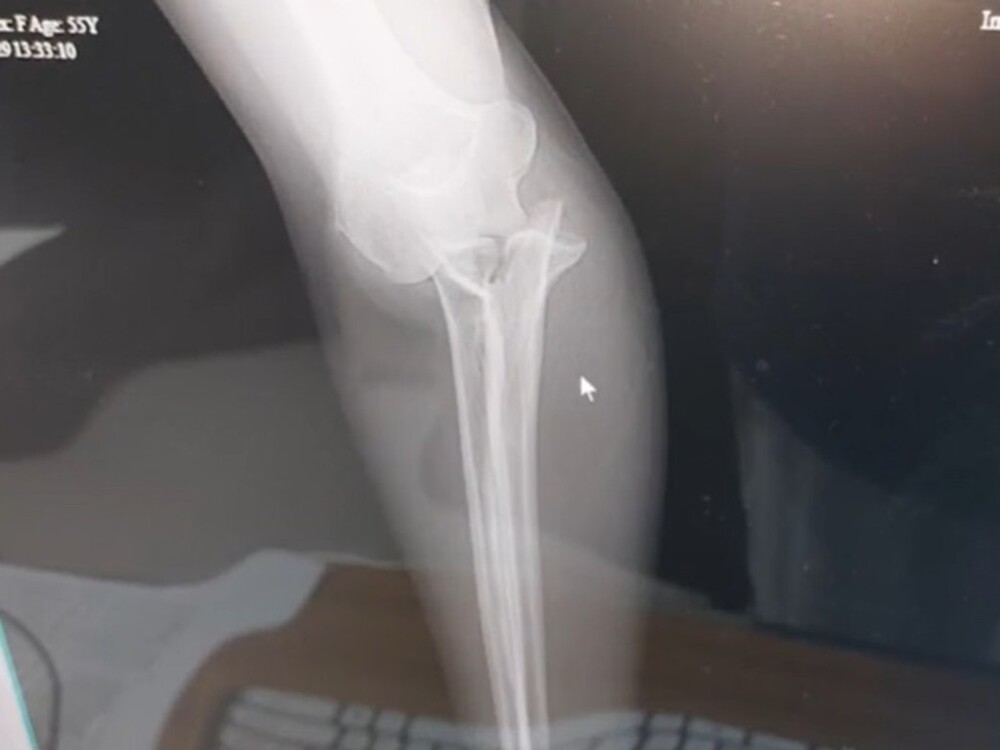

Рентгеновский снимок руки.

Администрация парка предложила пострадавшей лёд, но когда боль не прошла, женщину срочно отвезли в больницу, где сделав ренген, выяснили, то слон сделал весьма серьезный кусь - кости были сломаны.